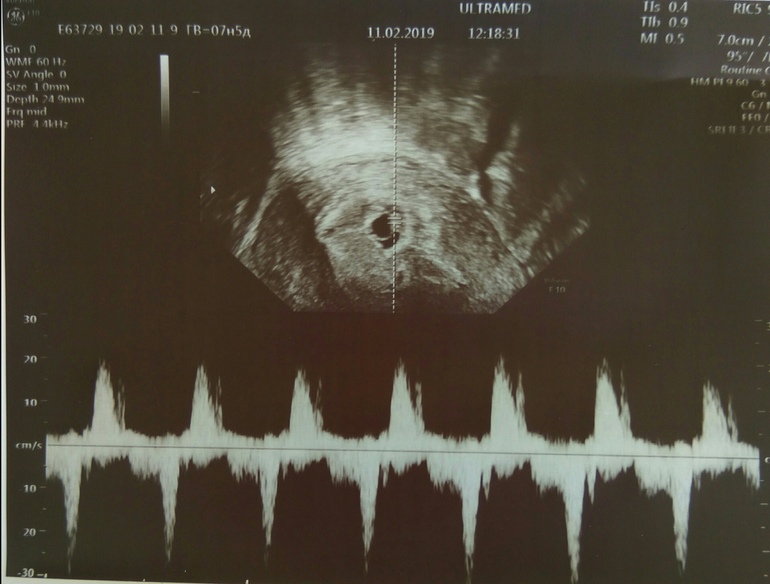

Сегодня сделала контрольное УЗИ в другой больнице: 6 недель и 1 день эмбрионального срока. КТР 4 мм, ЧСС 125 уд/мин.